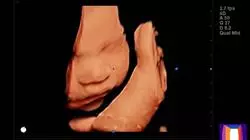

Le tecniche di imaging ricoprono un ruolo fondamentale nella gestione delle pazienti affette da patologia mammaria o ginecologica. I recenti progressi tecnologici consentono di restringere la diagnostica caratterizzando meglio le lesioni.

• Immagini reali ad alta risoluzione di patologie ginecologiche, nonché mammarie e dei relativi annessiç